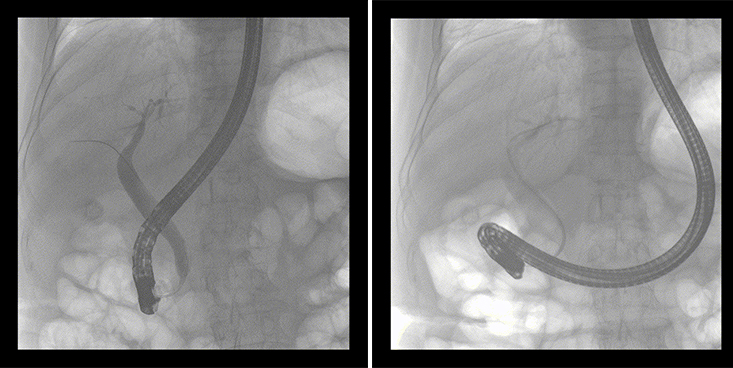

ERCP(经十二指肠镜下逆行胰胆管造影)现已成为比较成熟的微创介入技术,被广泛的应用于临床,ERCP也是消化内镜领域难度大、风险大、技术复杂的微创手术,其并发症多为致命性,ERCP手术对医生的要求很高,因此,ERCP医生又被称为“刀尖上的舞者”。因为手术难度较大,过程复杂,需要C形臂精准的配合,对影像清晰度的要求也非常高。

移动式平板中C为本次ERCP手术提供实时无损高清影像,帮助医生精准定位。“成像效果非常棒!完全不输国际大牌的医学影像设备……”鼓楼医院江北国际医院内镜中心手术团队对糖心vlog 移动式平板中C的成像效果给与了高度的评价。

移动式平板中C术中影像

在消化内科主任的领导和多科室全力配合下,南京鼓楼医院江北国际医院成功完成了首例ERCP手术。